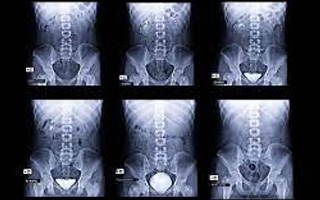

• IVP: An IVP (intravenous pyelogram ) is an imaging test used to look at the kidneys and ureters. The ureters are the narrow tubes that carry urine from the kidneys to the bladder. During the test, the radiologist injects a contrast dye into one of your veins. During an IVP, contrast dye is injected into a vein using an intravenous (IV) line. The dye travels through your bloodstream to your kidneys, which filter it out. The dye collects in the organs of your urinary tract and makes them look bright white on the x-rays.

• MCU: An MCU (Micturating Cysto-Urethrogram)is an x-ray test of the bladder as it fills and empties. It checks to see if the urine is flowing backwards from the bladder up towards the kidneys.